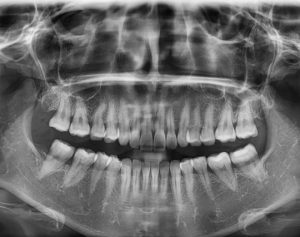

¿Por qué son necesarias las radiografías?

La realización de radiografías tiene como objetivo detectar posibles problemas o afecciones que a través de la exploración oral no se pueden determinar. Como por ejemplo:

- Agenesia dental

- Caninos incluidos

- Posiciones de cordales

- Afecciones en el hueso

- Caries radiculares

- Ortopantomografía